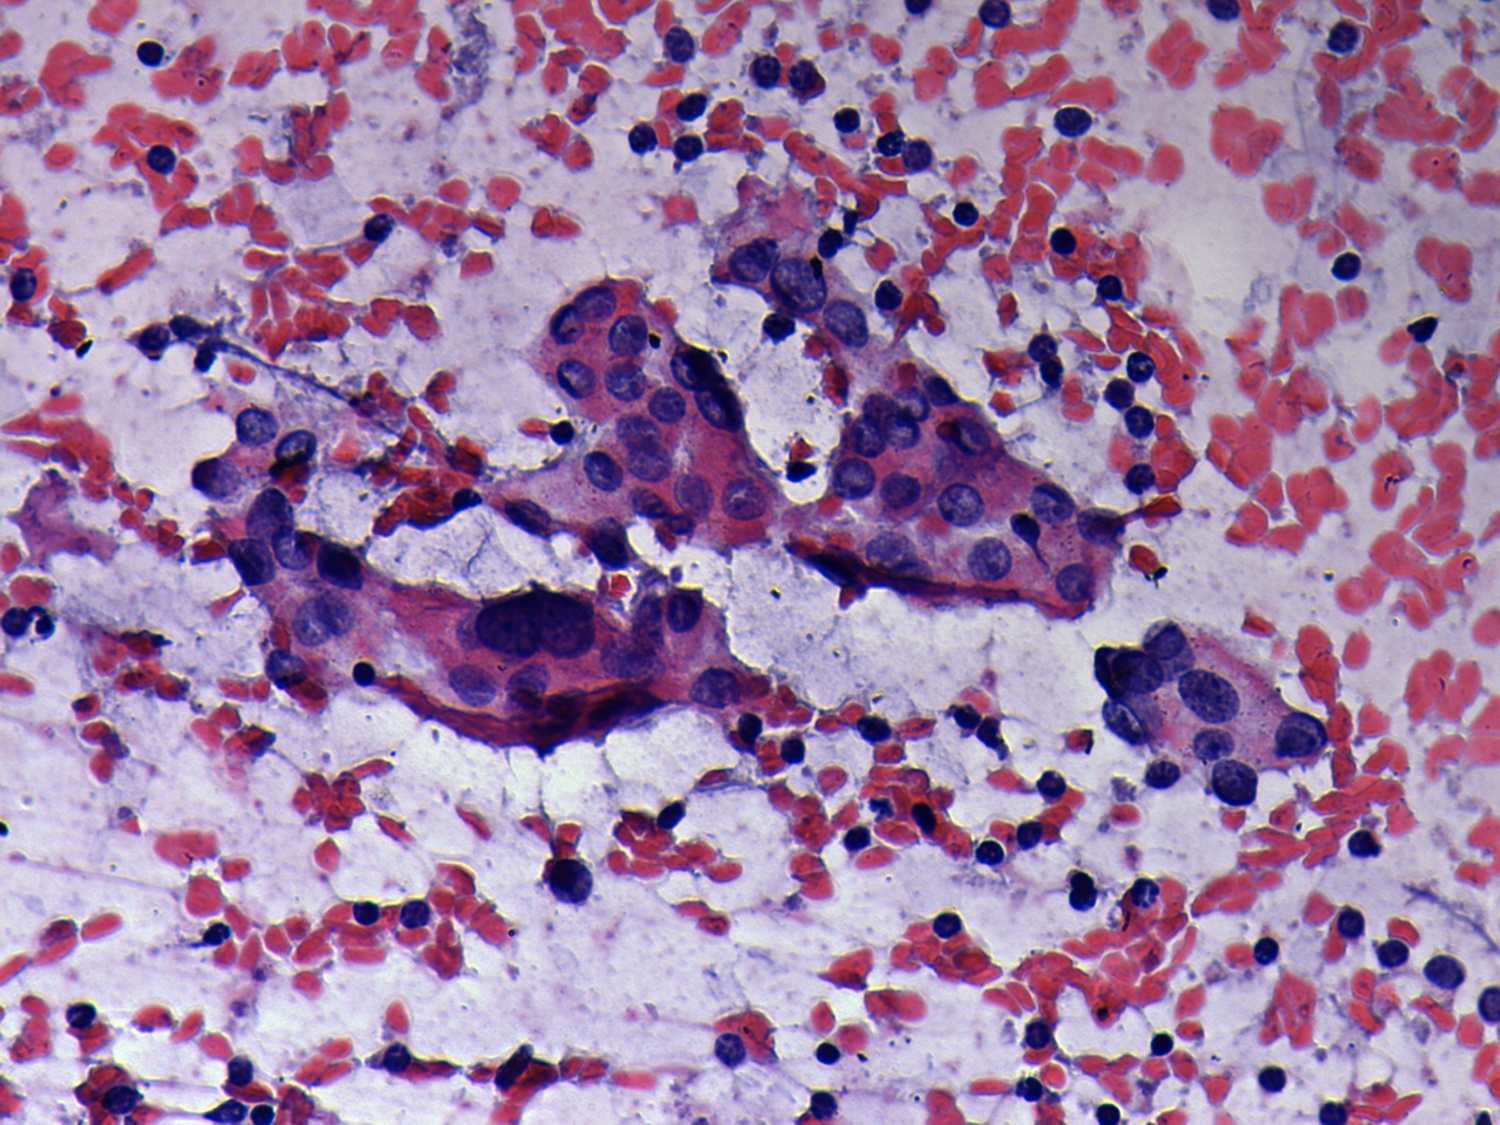

Chronic lymphocytic thyroiditis - Case 39. (cytologic picture 4)

Pap-smear, 400x. Follicular cells vary in shape and size.